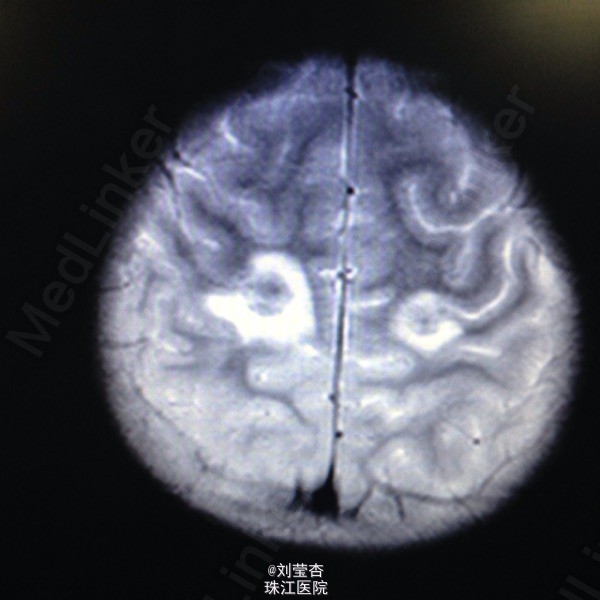

患儿女,3岁,因“咳嗽、流涕6天,发热5天,抽搐1次”入院。患儿接触家猫后出现流清涕,伴咳嗽,为间断单声咳,2天后出现发热,热峰39.5℃,予退热处理,患儿仍有反复发热,后患儿出现双眼向中上方凝视,双眼眼周肌肉抽动,伴口角流涎,无伴口周发绀、牙关紧闭,神志清楚,呼之可应,体温不详,四肢末梢温暖,四肢肌张力不高,持续约1分钟后可自行缓解。到当地医院就诊,查血常规:白细胞10.8G/L,中性粒细胞66.1%,淋巴细胞百分数27.1%,血红蛋白110g/L,血小板272 G/L,CRP4.2mg/L;胸片示支气管炎;头颅CT示右侧颞叶、双额叶多发散在脑出血。予吸氧、退热、抗感染、抗炎、补液、降颅压、止血等处理,患儿未再出现抽搐,患儿仍有反复发热,家属要求转我院进一步治疗。

查体:浅昏迷,反应一般,CRT2s,左侧耳后级颌下可触及3个肿大淋巴结,大小为0.5*0.5cm,质软,可活动,无压痛,与周围组织不粘连,双侧瞳孔等大不等圆,左侧瞳孔3mm,右侧瞳孔2.5mm,对光反射灵敏,口腔黏膜可见散在溃疡,咽部粘膜充血,双侧扁桃体Ⅰ度肿大,充血,未见黄白色脓点及分泌物,颈部稍抵抗,双肺呼吸音粗糙,可闻及大量痰鸣音,脑膜刺激症Kernig征可疑阳性,Brudzinski征可疑阳性。病毒八项:RUBE-IgG 26.8IU/Ml,CMV-IgG 117U/Ml,HSV-IgM 2.3S/CO,HSV-IgG 21.0S/CO,病毒两项:EB病毒DNA定量<5.00E+02(阳性)拷贝/mL,巨细胞病毒DNA定量9.65E+02(阳性)拷贝/mL;脑脊液常规:无色,透明,RBC 420M/L,WBC 40M/L,红细胞形态基本正常,潘氏试验(-);脑脊液单纯疱疹病毒DNA定量:单纯疱疹Ⅰ型DNA定量4.79+03(阳性)拷贝/mL,单纯疱疹Ⅱ型DNA定量低于检测下限拷贝/mL。

诊断:1.病毒性脑炎(单纯疱疹病毒感染)2.支气管肺炎。入院后予抗炎、抗病毒、抗惊厥、脱水、降颅压、促醒、输血浆,改善循环、雾化吸入、维持水电质平衡、营养支持等治疗。